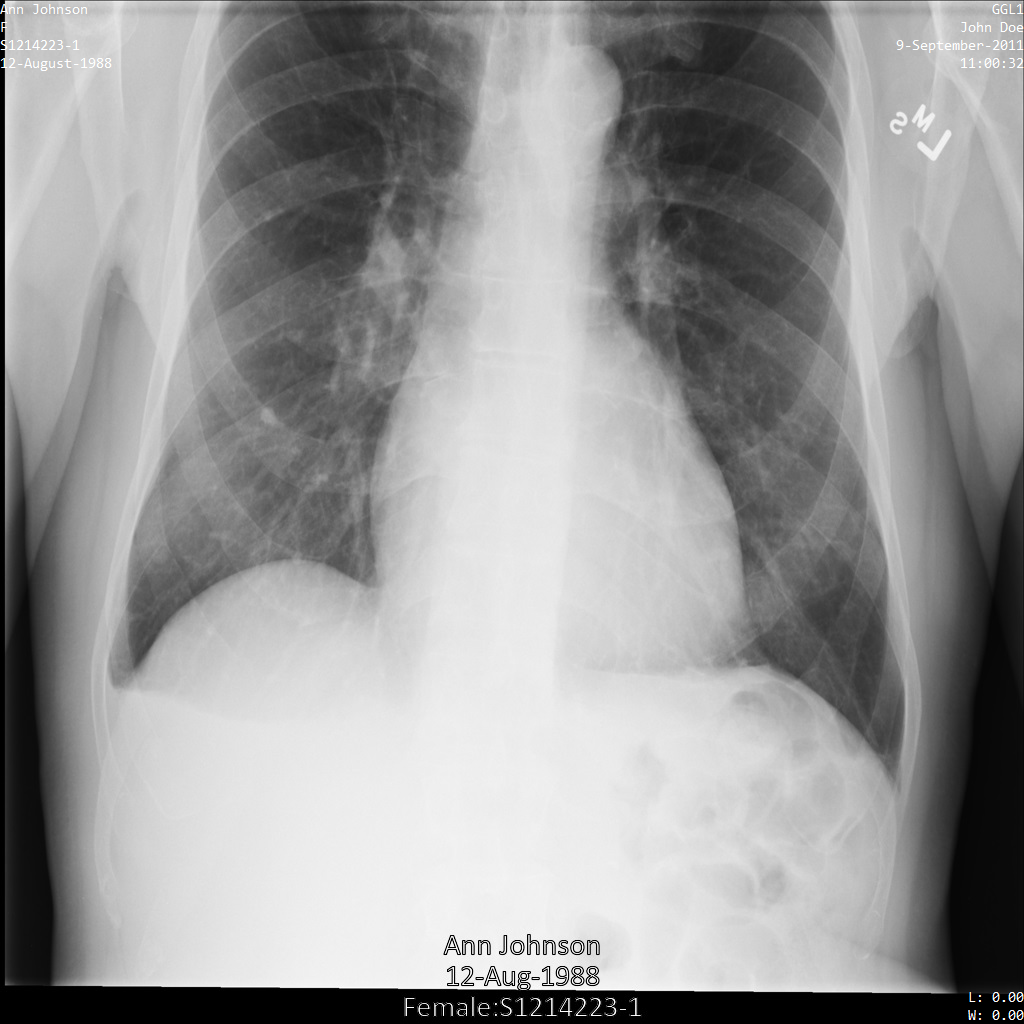

In jedem der folgenden Abschnitte finden Sie Beispiele zur De-Identifikation von DICOM-Daten mithilfe verschiedener Methoden. Für jedes Beispiel wird eine Ausgabe des de-identifizierten Images bereitgestellt. In jedem Beispiel wird das folgende Originalbild als Eingabe verwendet:

Sie können das Ausgabebild jedes De-Identifizierungsvorgangs mit diesem Originalbild vergleichen, um die Auswirkungen des Vorgangs zu sehen.

Nachdem Sie das Image an die Cloud Healthcare API gesendet haben, wird es wie folgt angezeigt. Während die Metadaten, die in den oberen Ecken des Bildes angezeigt werden, entfernt wurden, bleiben die eingebrannten geschützten Gesundheitsinformationen (PHI) unten im Bild erhalten. Informationen zum Entfernen des eingebrannten Texts finden Sie unter Eingebrannten Text aus Bildern entfernen.